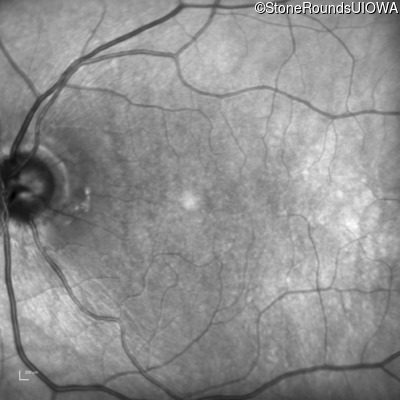

Infrared Fundus Photograph - Right - 20/200 -1 sc

Exemplar